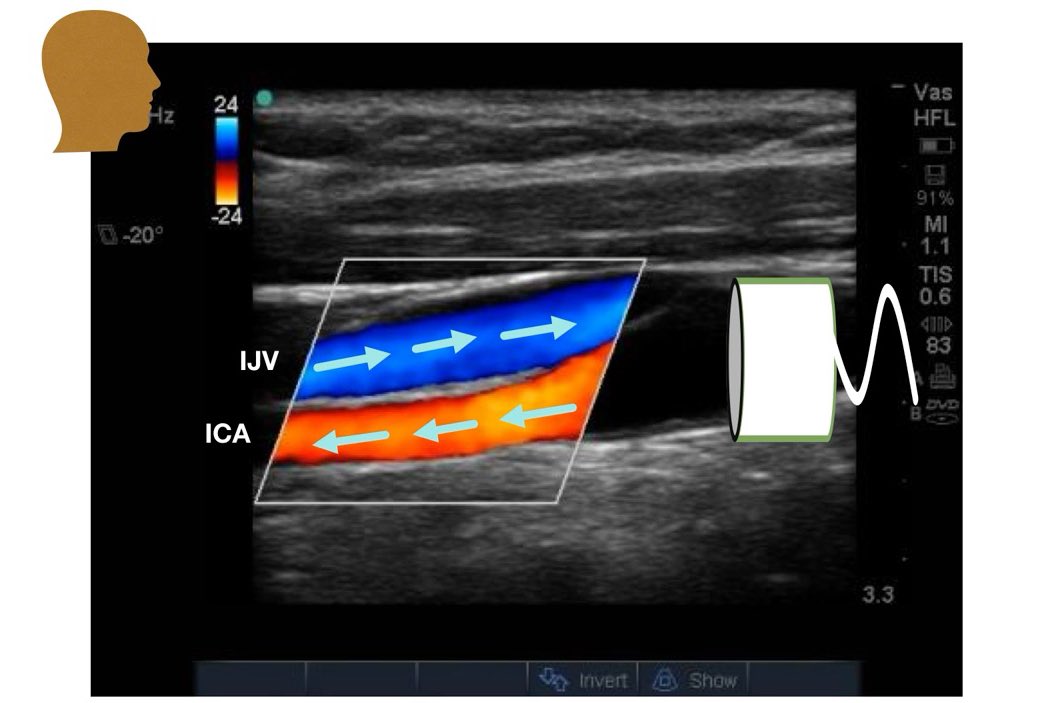

2- color map :

وهنا يهمنا الموجب أو السالب بس بغض النظر عن اللون سواء كان " ازرق او اصفر او احمر او فسفوري او اخضر مايهم لو تخيلت انهم صور حتى "

الموجب ( + ) = يدل على ان التدفق يركض للبروب

السالب ( - ) = يدل على ان التدفق هاج "يهرب" من البروب

حتى لو غيرنا وعكسنا السالب والموجب خلينا واحد تحت والثاني فوق والعكس

" مايهم مدام المبدأ ثابت "

( والكلام ينطبق على الـ spectral waveform بعد )

3- color box :

في ” الـ linear probe ” اذا فتحنا الـ box نشوف الزاويتين الي فوق ونرسم خط تخيلي لتحت ( الخط الي برا المربع هو الي يكون بجهة البروب ) ومنه راح نستنتج مكان البروب ( يمين او يسار )

طبق المعايير الي فوق على هالصورتين وبتعرف هل الاتجاه صحيح او لا